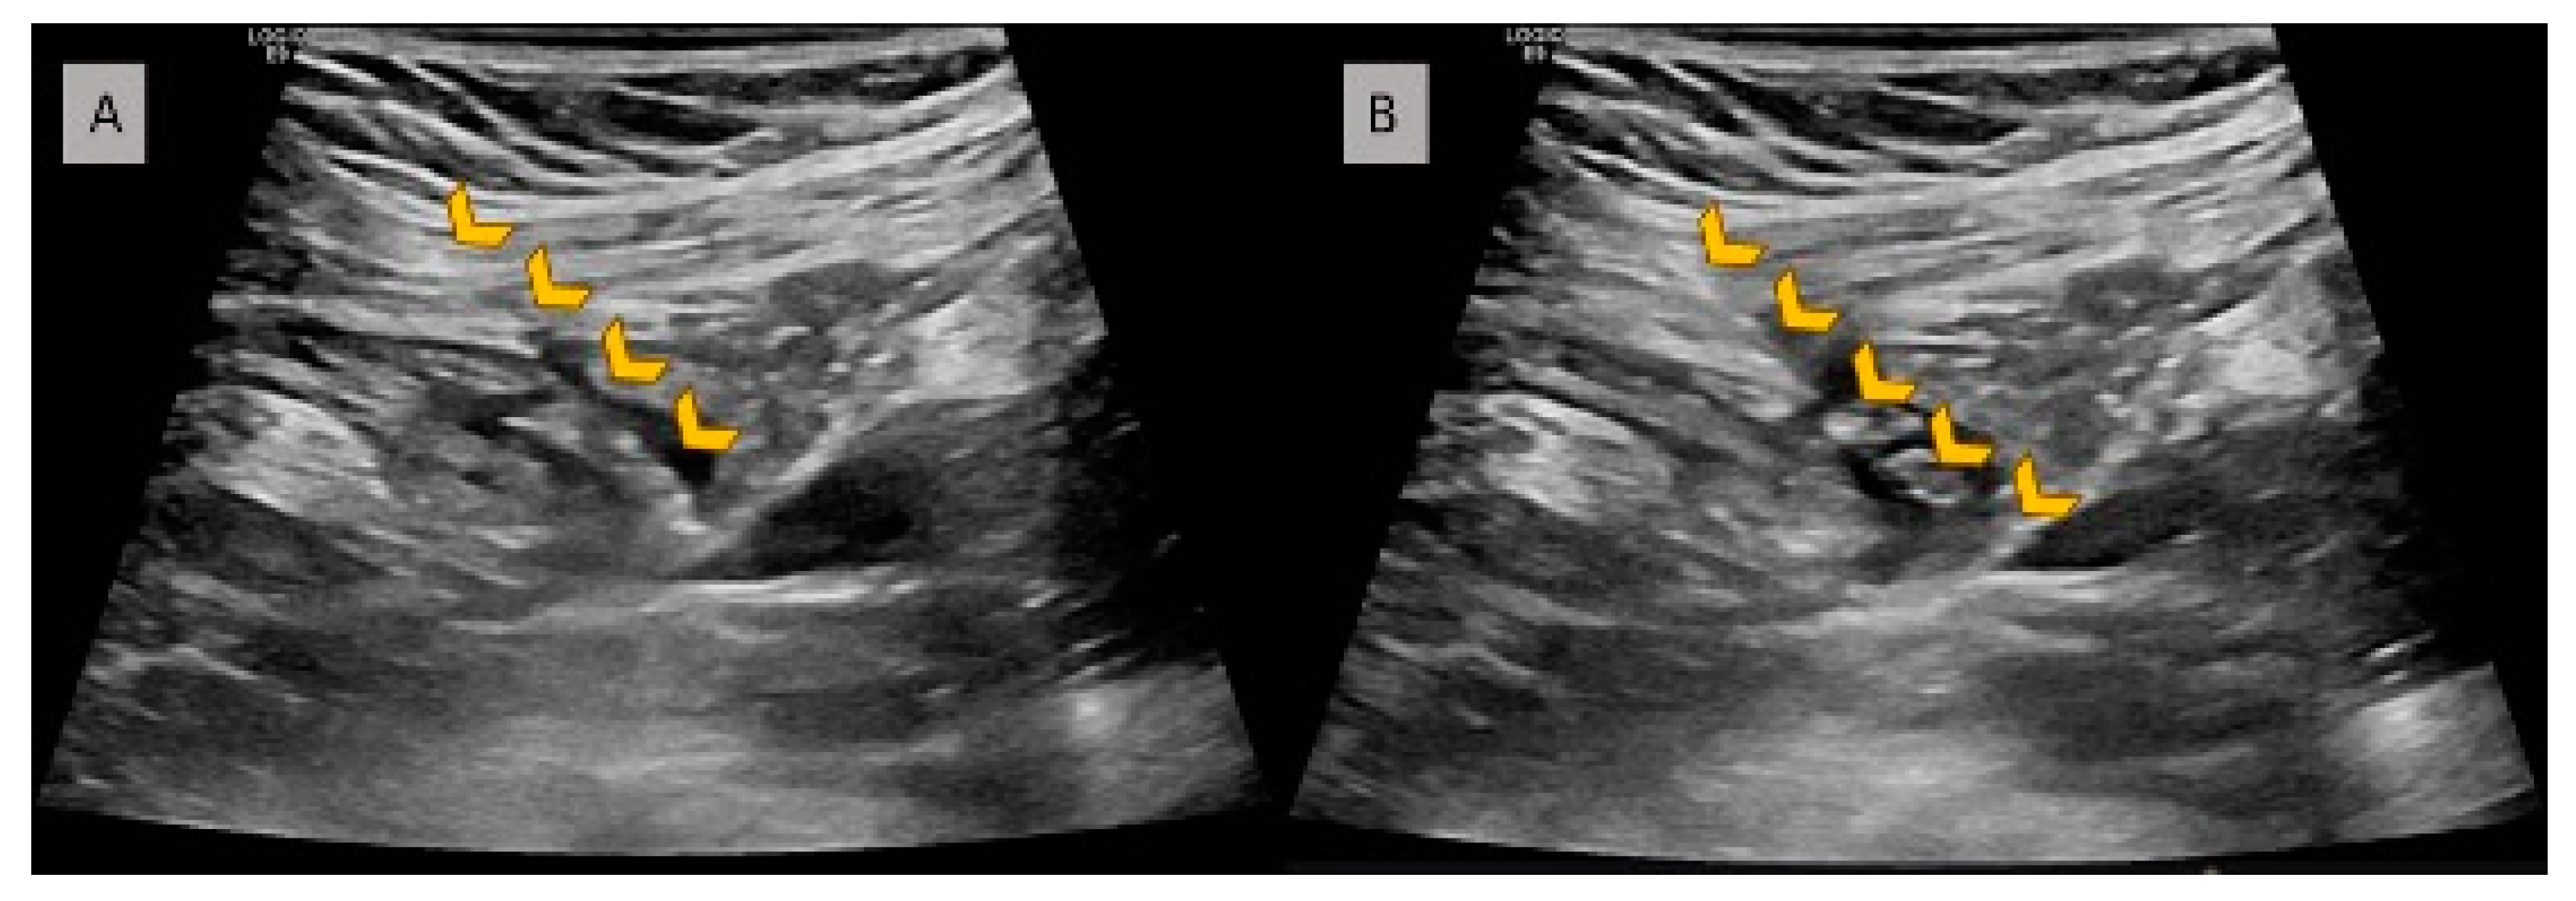

2.3. Procedure